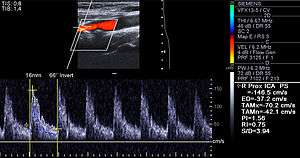

Examples of anatomical detection methods include coronary calcium scoring by CT, carotid IMT (intimal media thickness) measurement by ultrasound, and intravascular ultrasound (IVUS). Examples of physiologic measurement methods include lipoprotein subclass analysis, HbA1c, hs-CRP, and homocysteine. Both anatomic and physiologic methods allow early detection before symptoms show up, disease staging and tracking of disease progression. Anatomic methods are more expensive and some of them are invasive in nature, such as IVUS. On the other hand, physiologic methods are often less expensive and safer. But they do not quantify the current state of the disease or directly track progression. In recent years, developments in nuclear imaging techniques such as PET and SPECT have provided ways of estimating the severity of atherosclerotic plaques.